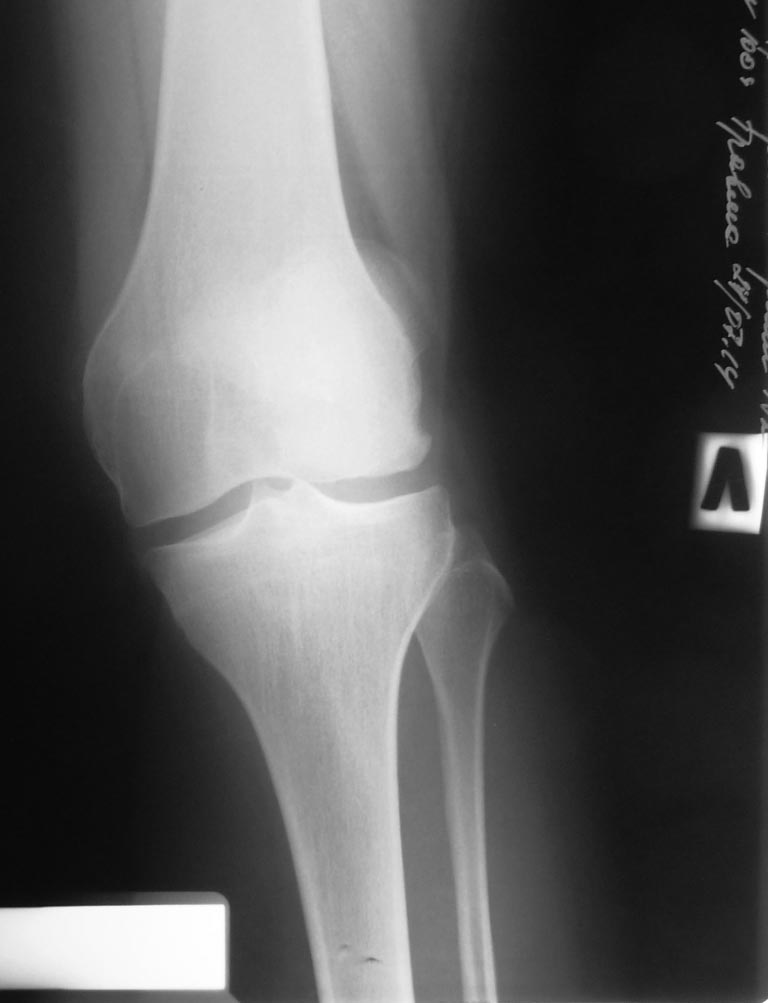

В травматологическом отелеении находится 16 летний юноша с пателло-феморальным артрозом, вторичной деформацией мыщелка бедра и надколенника. Глубокоуважаемые коллеги!Просим вас прокомментировать тактику лечения представляемого больного.Крупный ребёнок 16 лет. Избыточный вес. Не заинтересован в физических нагрузках. Обратился с жалобами на боли в левом коленном суставе при ходьбе. В 2011 году находился на стационарном лечении в нашей кинике по поводу застарелого перелома внутреннего края левого надколенника с разрывом капсулы сустава, хондромаляции наружного мыщелка бедра и гемартроза. За год до госпитализации перенёс двукратный спонтанный вывих левого надколенника. В отделении (март 2011 года) выполнена артроскопия, санация гиалинового хряща наружного мыщелка. Артропластика по Кемпбеллу. Рентгенограммы той поры не сохранились. Через 2 месяца после оперативного лечения ребёнок находился в отделении по поводу послеоперационной-посттравматической разгибательной контрактуры коленного сустава. После выписки больной исчез из поля зрения. Повторно обратился только в настоящее время. При осмотре: Походка не изменена. Вальгусная деформация коленных суставов: справа – 12, слева 15. Движения в коленных суставах в полном объёме. Выпот не определяется. Наружная ротация левой стопы 15-20 градусов. Левый надколенник латеролизован. При сгибании левого коленного сустава происходит наружная дислокация надколенника. Фото больного и результаты рентгенологического обследования прилагаем (будут выкладываться последовательно). Исходя из жалоб и результатов обследования, нами рассматривается следующий вариант хирургической помощи больному. Надмыщелковая остеотомия бедра, выполнение 15 градусов внутренней ротации дистального сегмента, его варизирующее отклонение на 15 град. до исправления вальгуса (анатомической оси конечности ). Очень сомневаемся в отношении вмешательства на поддерживающем аппарате надколенника. Мнения разделились: сделать латеральный релиз , либо не трогать совсем. Делать ли дупликатуру медиального отдела капсулы? Вызывает опасения неконгруентность суставной поверхности надколенника. Рассматриваем вариант V-образной остеотомии надколенника. Следует ли «подгонять» такой надколенник по мыщелку или оставить в надежде на постепенную перестройку. Как одна из ожидаемых проблем после выполнения вмешательства – резкое ограничение сгибания, так как в настоящее время надколенник «уезжает» с мыщелка при сгибании – что, скорее всего, вызвало укорочение квадрицепса и собственной связки надколенника. Может ли появиться необходимость вмешательства на собственной связке и бугристости одномоментно?Больной не настаивает на оперативном лечении. Родители же согласны с необходимостью коррекции. Как один из вариантов – не трогать нам его совсем. Живёт же . Будем благодарны за соображения, подсказки и опыт похожих ситуаций.

А вариант с переносом бугристости б/б кости не рассматриваете? Контралатеральная конечность тоже в вальгусе, но там же надколенник не латерализуется. Вальгус, наверное, не основной момент нестабильности. На аксиальном снимке - явная дисплазия наружного мыщелка. Не исключен ещё и вариант patella alta - на фотографиях не очень понятно. Наверное, всё же без укрепления медиального отдела и релиза латерального будет не обойтись.

Судя по предсавленным снимкам, у парня ретровесионная деформация шейки бедра, вальгусная деформация бедра, внутренняя ротация голени,гипотрофия наружного мыщелка бедра, возможно высокое стояние надколенника!!!